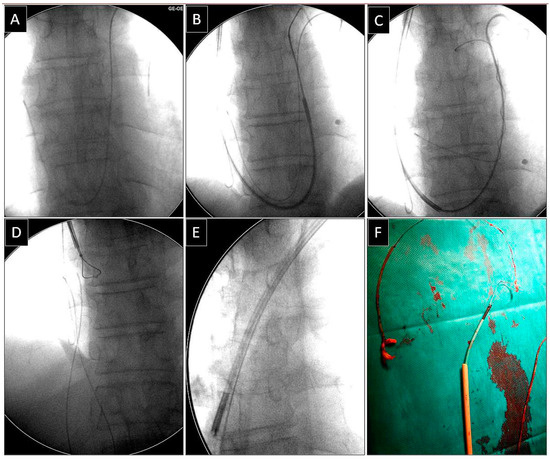

Extraction of Leads with Migrated Proximal Ends into the Cardiovascular Space

| Methods of removing fractured migrant leads | |||||

| Superior approach | 6 (15.39) | 3 (23.08) p = 0.832 | 3 (23.08) p = 0.832 | 5 (71.43) p = 0.007 | 17 (23.61) |

| Combined approach | 3 (7.69) | 3 (23.08) p = 0.316 | 1 (7.67) p = 0.548 | 1 (14.29) p = 0.874 | 8 (11.11) |

| Femoral approach | 29 (74.36) | 7 (53.85) p = 0.298 | 8 (61.54) p = 0.596 | 1 (14.29) p = 0.001 | 45 (62.50) |

| Lasso/basket inside 13 FWS, NE (dilatation) | 31 (68.89) | Lasso/basket 13, FWS, NE—femoral approach (dilatation) | 31 (43.06) |

| Lasso/basket inside another large sheath (polypropylene) (dilatation) | 5 (11.11) | ||

| Lasso/basket inside transseptal sheath (only pulling) | 9 (20.00) | Lasso/basket another large sheath—femoral (dilatation) | 5 (8.33) |

| Loop femoral approach (pulling, end release) | 35 (77.78) | Lasso/basket in CS sheath—superior approach (pulling only) | 1 (1.39) |

| Pig-tail + winding and shifting femoral (end release) | 7 (15.56) | Lasso/basket only—superior approach (pulling only) | 3 (4.17) |

| Pig-tail femoral (end orientation) | 3 (6.67) | Cardiac surgery | 2 (2.28) |

| Risk of MC-TLE procedure interrupted | 1 (1.39) | Loop femoral approach (pulling, end release) | 42 (58.33) |

| Haemopericardium—rescue cardiac surgery | 1 (1.39) | Loop superior approach (pulling, end release) | 6 (8.33) |

| All: | 2 (2.28) | Pig-tail + winding and shifting femoral approach (pulling, end release) | 8 (11.11) |